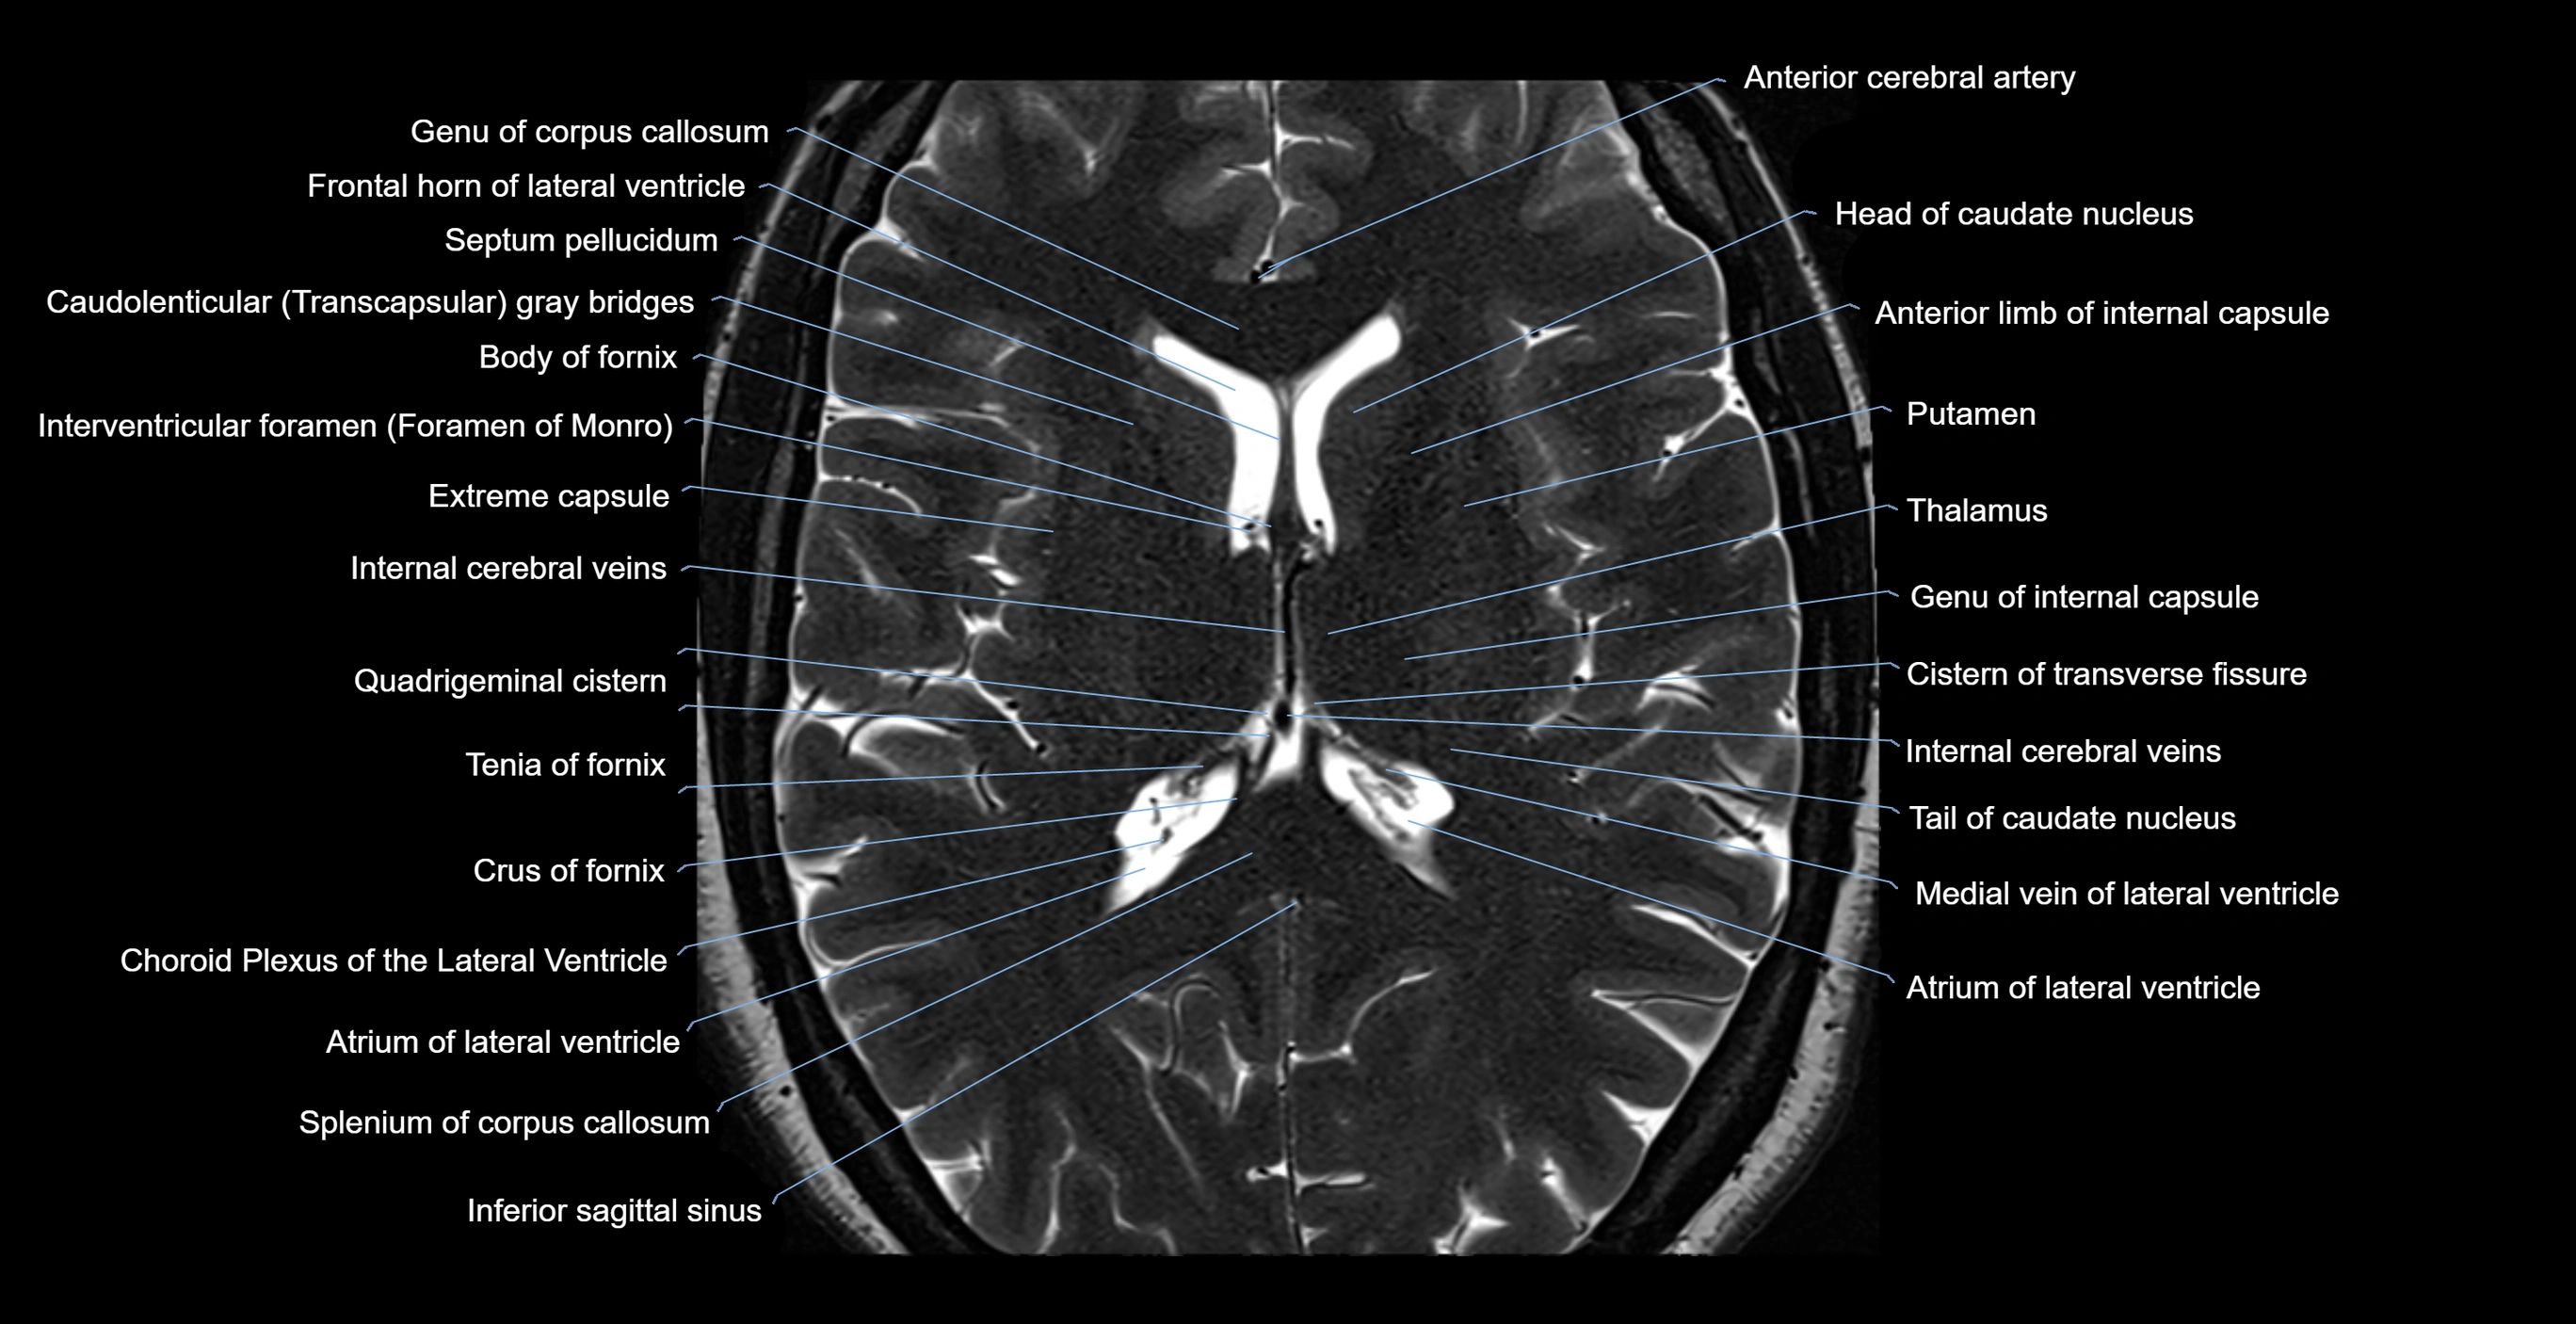

- Anterior cerebral artery

- Atrium of lateral ventricle

- Body of caudate nucleus

- Body of fornix

- Body of lateral ventricle

- Central part of lateral ventricle

- Cistern of transverse fissure

- Column of fornix

- Corona radiata

- Crus of fornix

- External capsule

- Extreme capsule

- Frontal horn of lateral ventricle

- Genu of corpus callosum

- Head of caudate nucleus

- Inferior sagittal sinus

- Internal cerebral vein

- Interventricular foramen

- Medial vein of lateral ventricle

- Occipital horn of lateral ventricle

- Posterior limb of internal capsule

- Quadrigeminal cistern

- Septum pellucidum

- Splenium of corpus callosum

- Superior thalamostriate vein

- Tail of caudate nucleus

- Tenia of fornix

- Thalamus

- genu of internal capsule